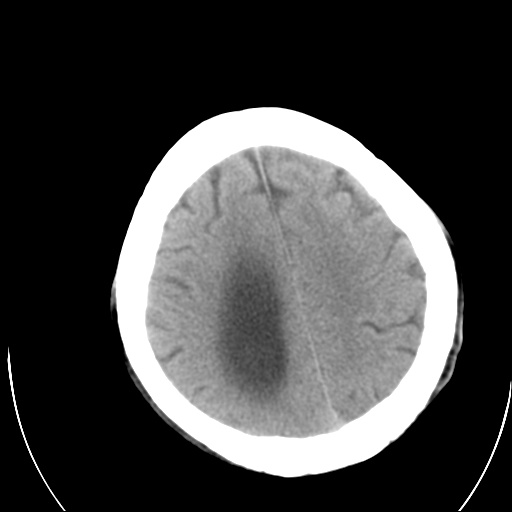

以下是引用泪洒红尘在2009-3-23 19:53:00的发言:[br]第四脑室以上脑室明显扩大,脑沟脑裂无明显增宽加深征象,符合交通性脑积水ct表现。

以下是引用xulianj在2009-3-23 20:31:00的发言:[br]右侧侧脑室扩大,中线结构左移,考虑梗阻性脑积水,建议mri检查。